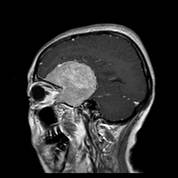

经查体,神经外六科吴杰主任诊断为:左侧蝶骨嵴占位性病变,考虑脑膜瘤可能性大。之后黄女士完善了相关检查,颅脑CT及CTA检查提示:左侧中颅窝底巨大占位病变,其内血管丰富,临近左侧大脑中动脉明显受压向上移位,考虑脑膜瘤;颅脑磁共振提示:左侧前中颅窝底巨大占位性病变,考虑脑膜瘤。介入栓塞提示:肿瘤主要由左侧脑膜中动脉额支、少量由左侧眼动脉脑膜支参与供血。

术前MRI可见左侧额颞巨大占位,增强均匀强化,考虑脑膜瘤